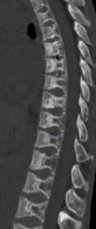

- Déformation en H des vertèbres (infarctus du centre du plateau)